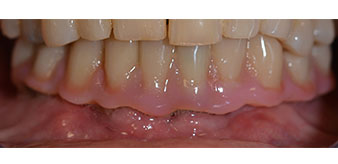

La patiente âgée de 64 ans présente une denture résiduelle des dents 38, 33 et 43 et une prothèse amovible mandibulaire stabilisée par crochets (Fig. 1 et 2).